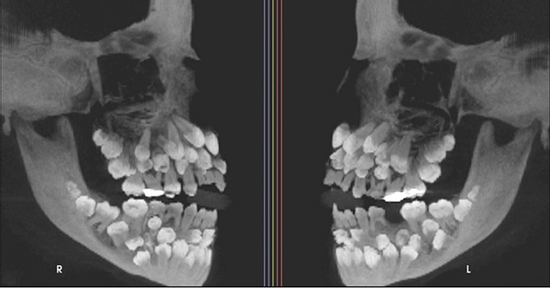

Đi nhổ răng sữa, bé gái khiến nha sĩ sốc nặng khi có 81 chiếc răng

Đi nhổ răng sữa, một bé gái 11 tuổi đã khiến nha sĩ sốc nặng khi phát hiện phim chụp X-quang cho thấy cô bé có 81 chiếc răng trong miệng.